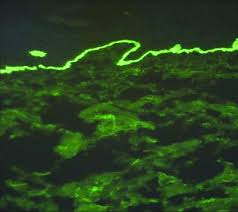

- The direct immunofluorescence test shows intercellular IgG and C3 deposits in a typical fishnet pattern.

- The RITUX 3 trial, which was published in The Lancet (2017), demonstrates that rituximab delivers better treatment results than standard immunosuppressive drugs. The image shows direct immunofluorescence results through the application of an anti-IgG antibody.

Microscopic image of direct immunofluorescence using an anti-IgG antibody.